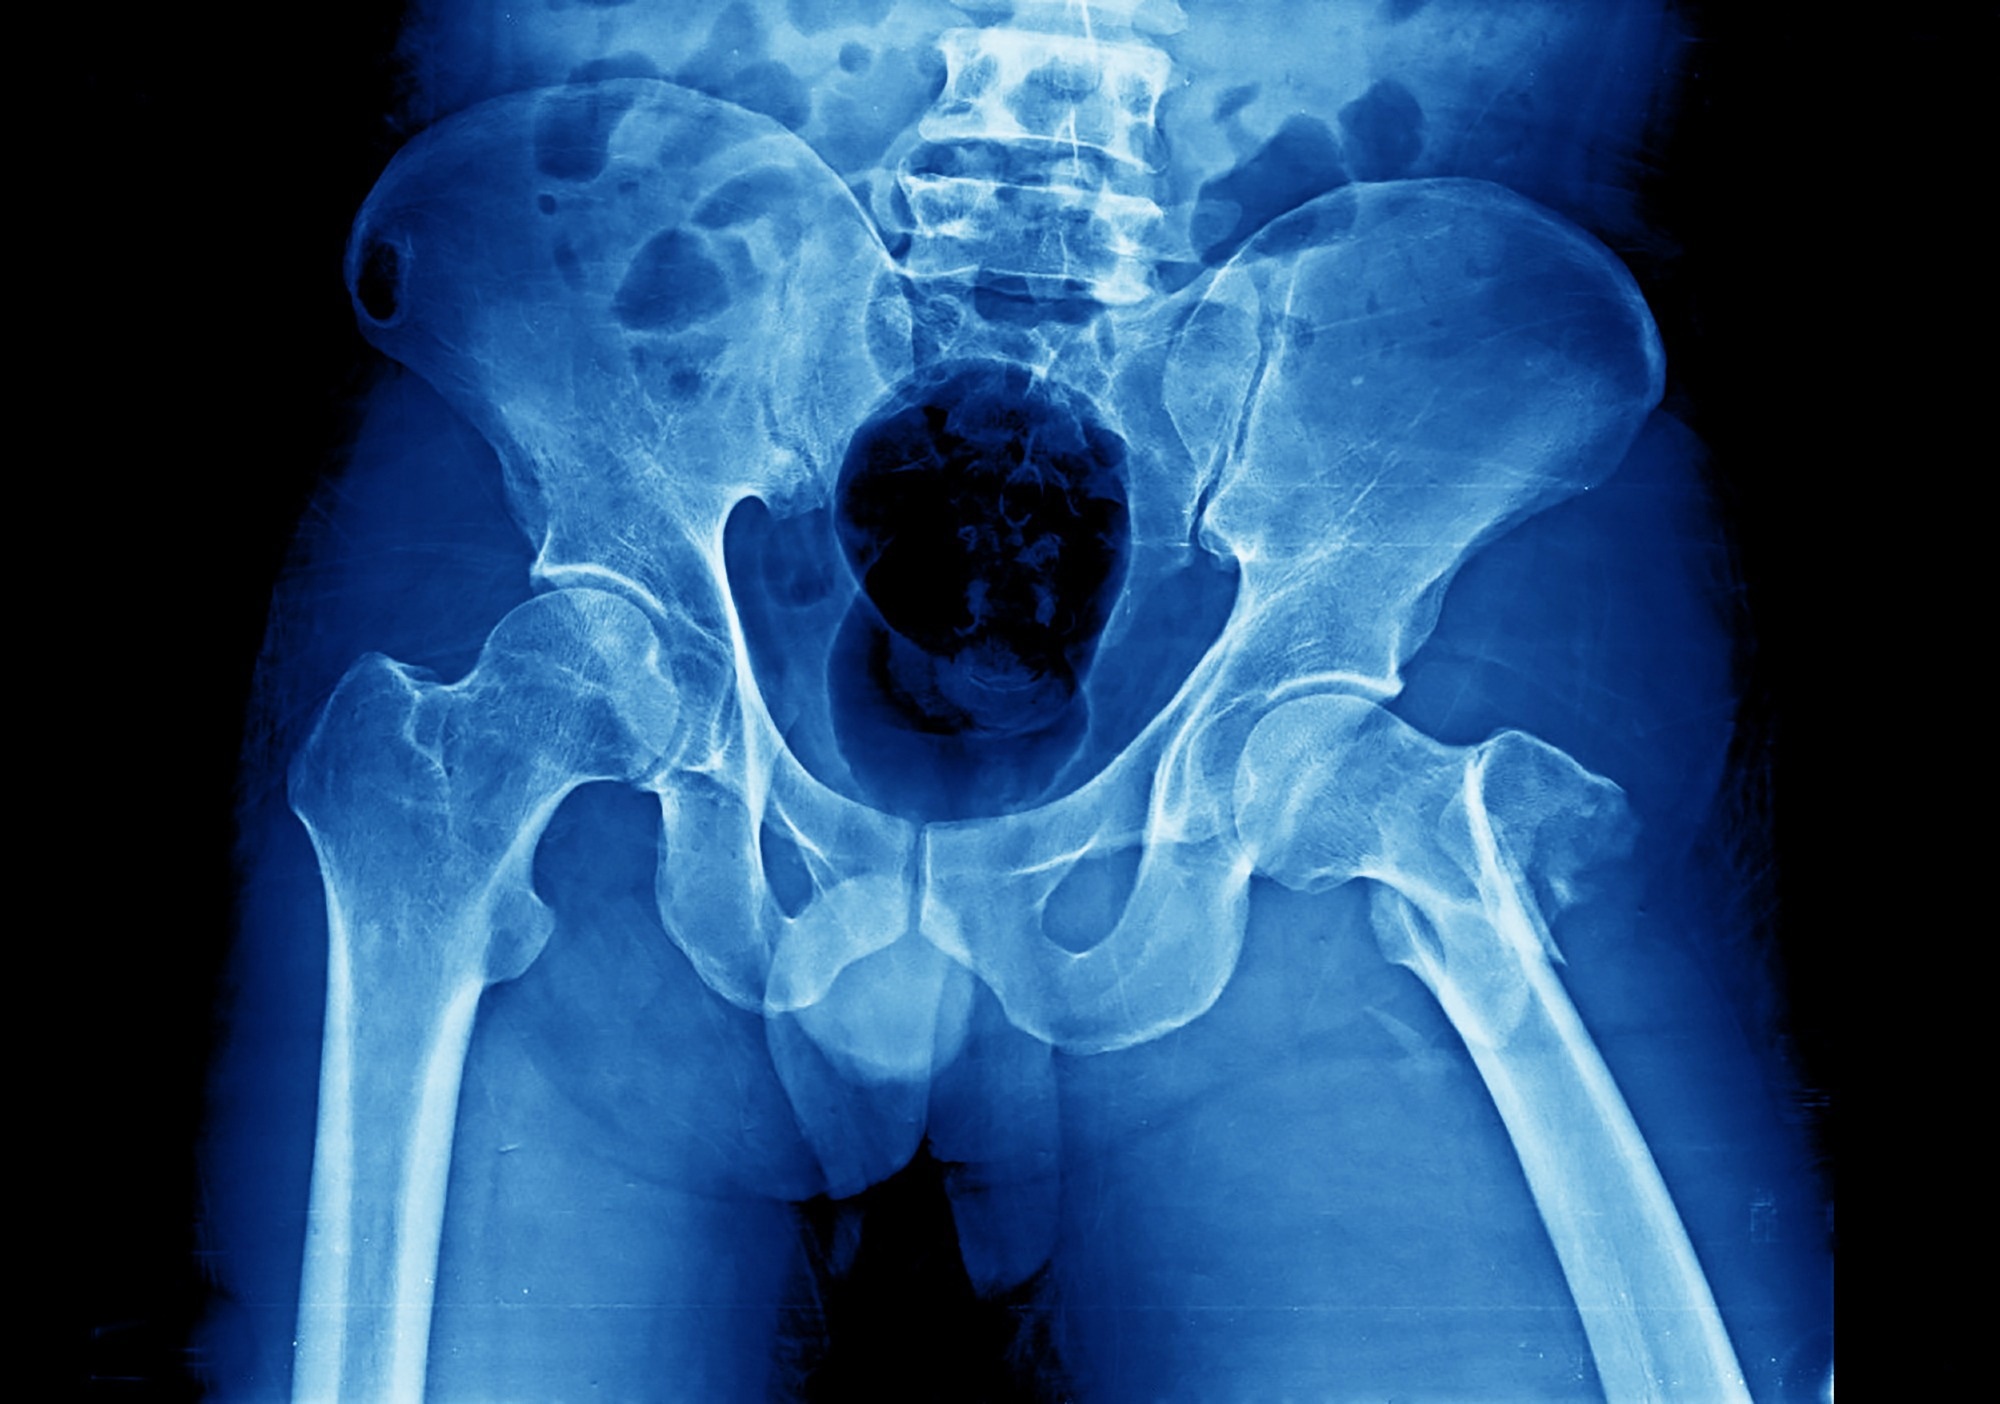

Study: ‘Skeletal Age’ for mapping the impact of fracture on mortality. ​​​​​​​Image Credit: Yok_onepiece / Shutterstock​​​​​​​Study: ‘Skeletal Age’ for mapping the impact of fracture on mortality. ​​​​​​​Image Credit: Yok_onepiece / Shutterstock

In the study of more than 1.6 million adults, the scientists found that a bone fracture was associated with a loss of one to seven years of life, depending on gender, age, and bone site.

UTS Distinguished Professor Tuan Nguyen, the project leader, says the risk of premature death is particularly high for patients who suffer a hip fracture, with 30% of patients dying within a year of the fracture.